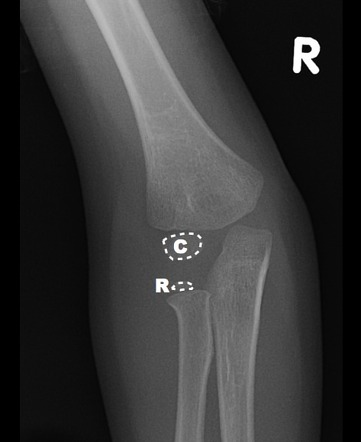

Оссификаты Локтевого Сустава: Диагностика и Лечение

Раздел: Секреты мастерства